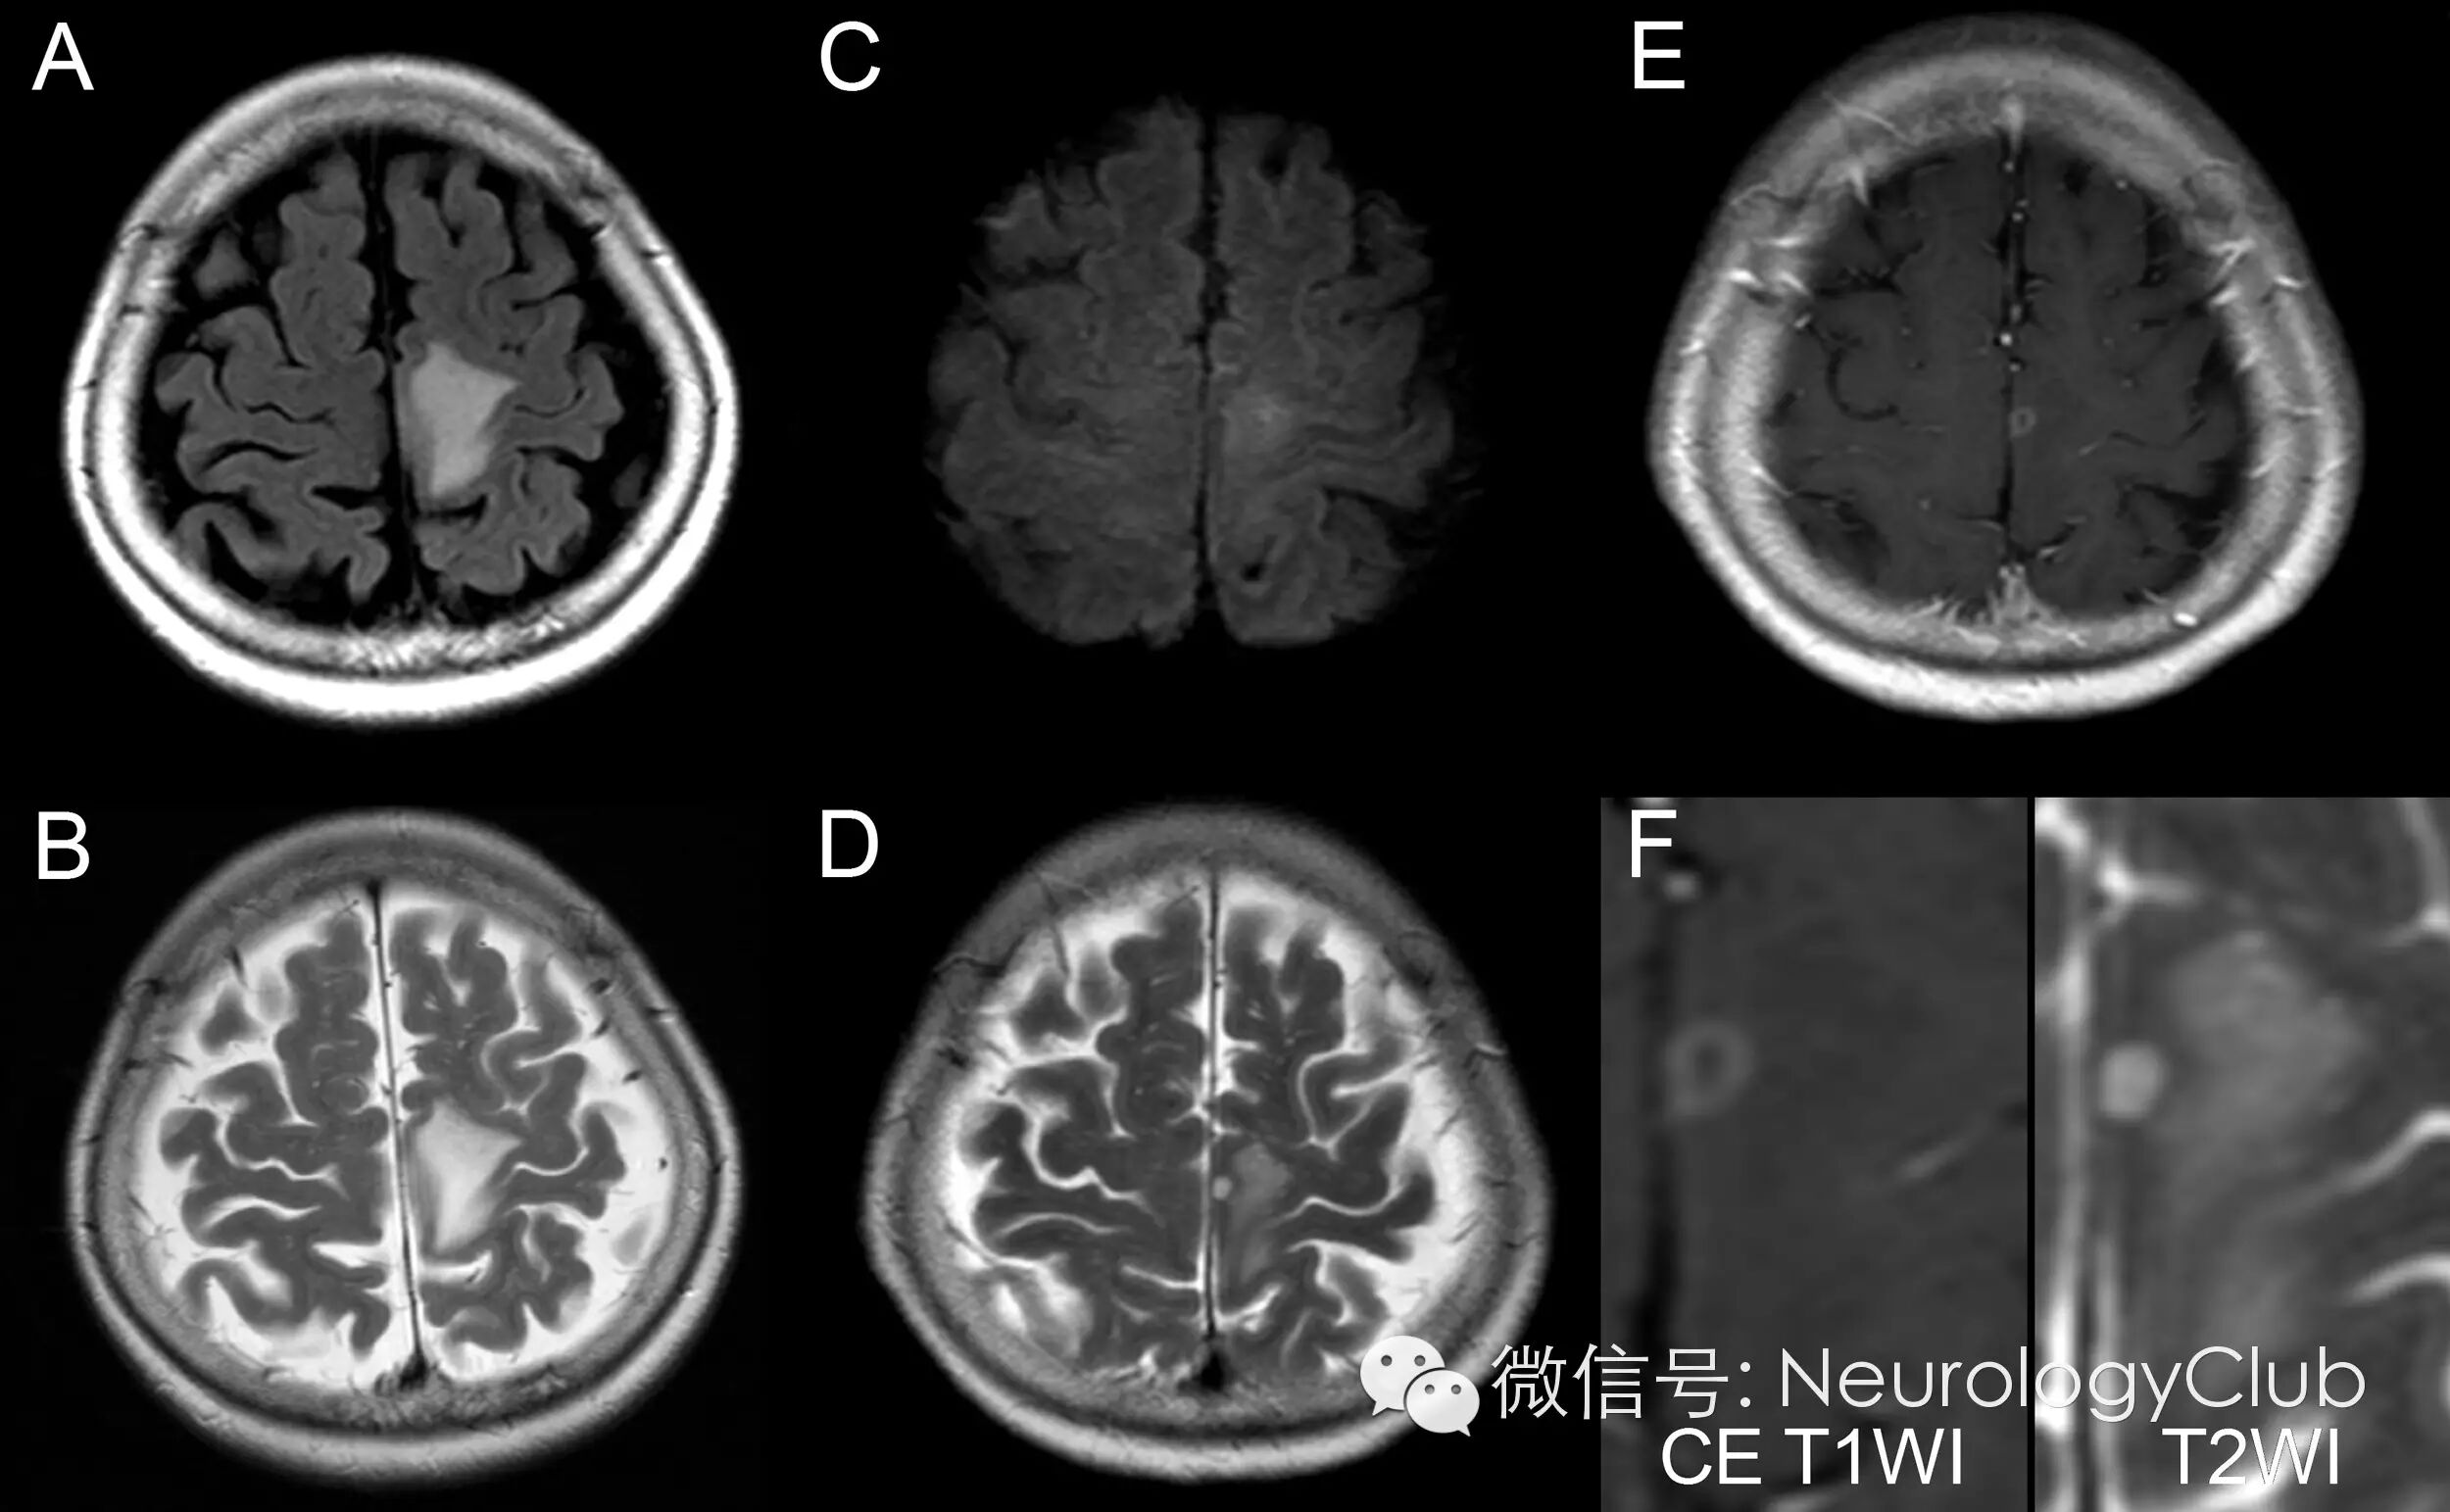

(图1:起病后3天的MRI:左侧大脑皮质FALIR[A]与T2WI[B]高信号;起病后36天,已经口服激素治疗后的MRI:[C]DWI可见左侧额叶轻度高信号病灶;[D]T2WI小病灶高信号伴周围水肿;[E]T1增强病灶呈环形强化;[F]病灶放大图)

头颅MRI可见左侧额叶一小环形强化病灶伴周围水肿(图1)。基于上述资料,患者初步诊断为肺癌脑转移和癌性脑膜炎。因患者有夜间呼吸困难开始给予无创正压通气。

同样的,中枢神经系统隐球菌病中,免疫健全患者的影像学与见于免疫缺陷患者的典型影像学表现大不相同。前者的典型MRI可见脑回样软脑膜强化,V-R间隙内小囊样或结节状强化;也可出现单发强化的蛛网膜囊肿和单发环形强化实质性病灶。病灶中T2低信号也被认为是脑隐球菌瘤的特征性表现。但有些学者认为脑隐球菌瘤很少出现环形强化,且单发的隐球菌瘤罕见。本例患者最初的头颅MRI表现为小的单发环形强化的隐球菌瘤伴灶周明显水肿。MRI上环形强化可能代表了患者具有免疫反应的能力。新型隐球菌有多糖荚膜,即使在免疫健全的患者中也可保护其免受宿主的炎症反应。这可能解释中枢神经系统隐球菌病较低的病灶周围水肿发生率。但有一些病例报道提示中枢神经系统隐球菌瘤可伴明显水肿,一般这种瘤体较大。而本例患者菌瘤很小,水肿却很明显。此外,病灶中并未出现T2低信号,导致一开始误诊为脑转移瘤。